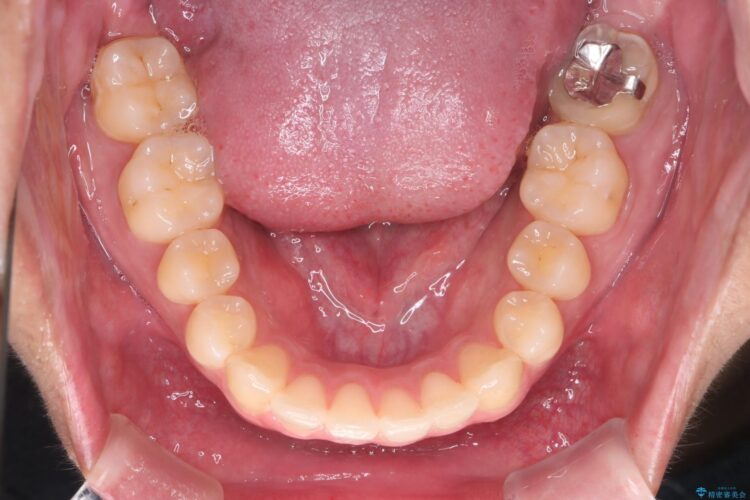

目立ちにくいクリア装置で八重歯とがたつきの改善

非抜歯での治療だったため、1年半以内という短い期間で矯正を終了することができました。主訴であった八重歯とがたつきが改善され、大変ご満足いただきました。

精密検査の結果、抜歯の必要はないと判断しました。臼歯を遠心移動させ、歯列をワイヤーで整えることでスペースを確保し、IPR(歯と歯の間を削る処置)を加えて歯並びを綺麗にする治療計画を立てました。